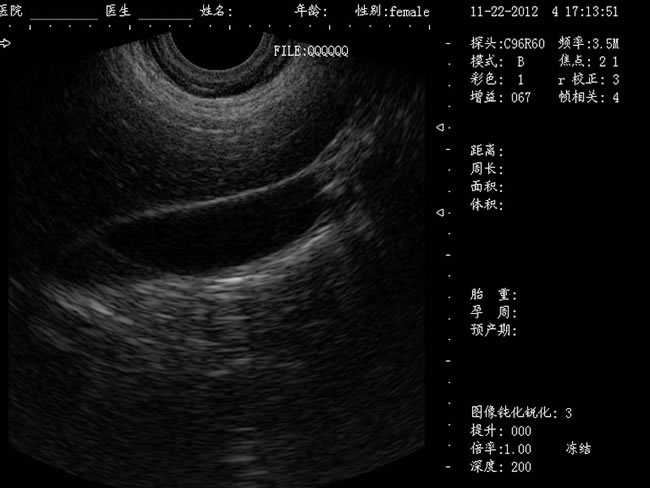

定位精確 手術(shù)效率高:實(shí)時(shí)動(dòng)態(tài)頻率掃描等全數(shù)字超聲成像技術(shù)、生成精確的圖像引導(dǎo)手術(shù)器械迅速到大手術(shù)位置,避免損傷子宮內(nèi)膜和子宮穿孔的現(xiàn)象,即減輕了患者的痛苦又極大提高了手術(shù)效率。

有效提升系統(tǒng)的穩(wěn)定性、可靠性:實(shí)時(shí)動(dòng)態(tài)孔徑成像,充分保證圖像的精度和清晰度

選配:CXA60R/3.5MHz 凸陣探頭

隨著醫(yī)療技術(shù)水平的提高,目前婦產(chǎn)科手術(shù)中所應(yīng)用的相關(guān)設(shè)備也有了加大的改進(jìn)。尤其是在人工流產(chǎn)手術(shù)中,將B超婦產(chǎn)科手術(shù)監(jiān)視儀應(yīng)用到手術(shù)過程中,彌補(bǔ)傳統(tǒng)手術(shù)中所采用設(shè)備的不足之處,減輕手術(shù)中患者的疼痛感覺,使得手術(shù)順利的完成。這種儀器相比于傳統(tǒng)的儀器來說,其在操作上更為方便和簡單,能夠?qū)θ焉锓磻?yīng)有很好的療效。